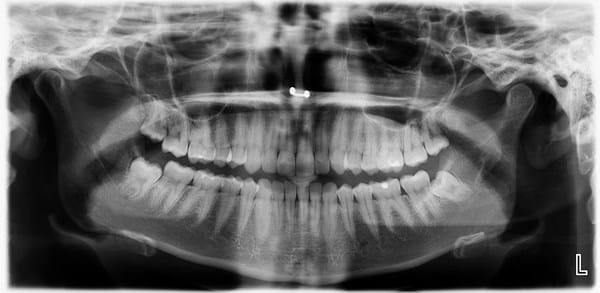

Mi problema es el siguiente. Mordiendo un caramelo muy duro se me rompió la primera muela del lado derecho (hace una semana). No es la gran cosa, sino sólo una esquina. Esa muela ya estaba agrietada y empastada, por lo visto se terminó de romper. Me duele por ejemplo al tomar agua, tengo sensibilidad en esa esquina rota pero nada más. Me dijeron que tengo que hacerme una endodoncia, pero tenía la idea de que eso sólo es necesario cuando el nervio está infectado o cuando el daño es muy grande. ¿Será realmente necesario o con un empaste se soluciona? Adjunto la imagen de una ortopantomografía que me hice ayer, allí se ve la muela rota y el nervio más inflamado de lo normal (comparado con las otras muelas).